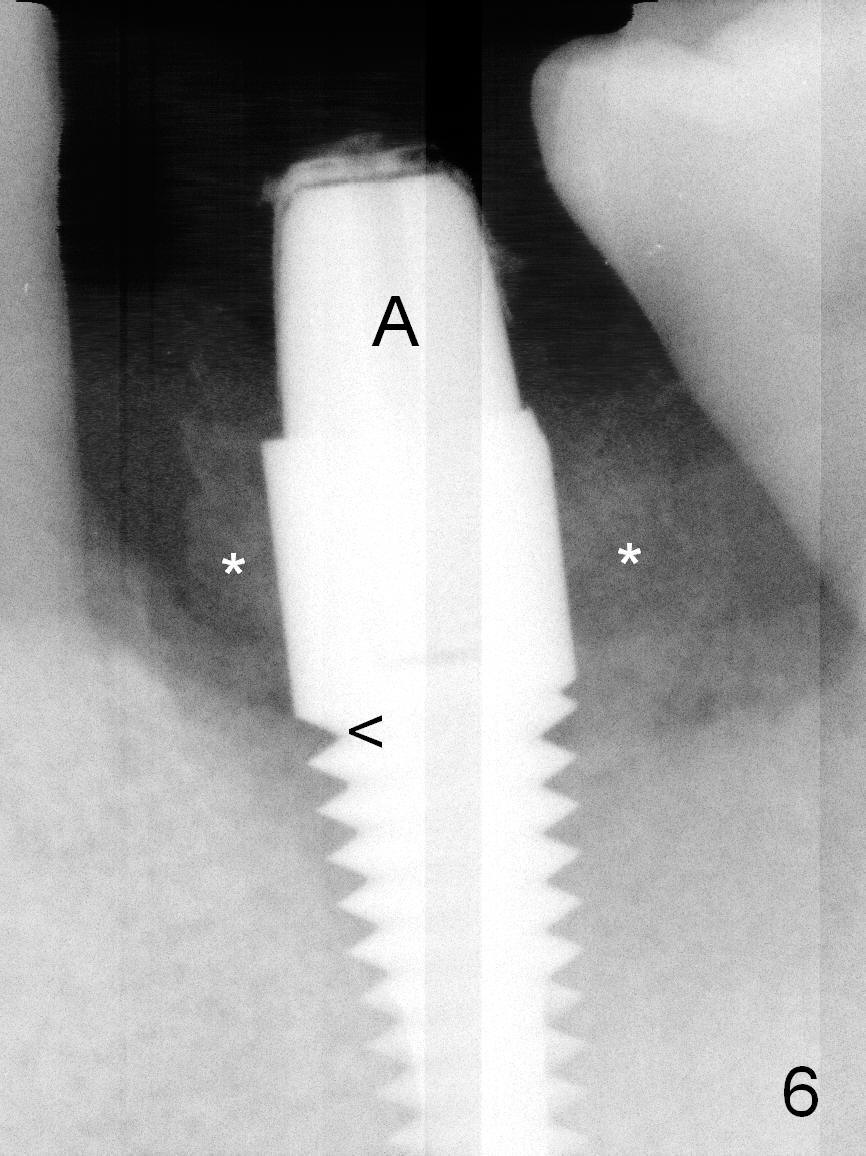

When the patient returns for #19 extraction and immediate implant, there is buccal (Fig.1 *) and lingual gingival swelling. The distobuccal root is exposed (D). Both the buccal and lingual walls are low. There is no septum. After removal of granulation tissue, an osteotomy is established in the bottom of the socket (slightly mesiolingually). The depth is approximately 3 mm in new bone (half of 6 mm and arrowhead). When the depth increases approximately 6 mm in new bone (Fig.3 arrowhead with 6x20 mm tap (T) in place), the Inferior Alveolar Canal is still invisible in PA. Panoramic X-ray has to be taken (Fig.4). So far infiltration anesthesia has been administered. When #2 sensor is inserted in the lingual vestibule, the patient feels pain and nausea. Lingual Nerve block is provided. The patient feels pain when further osteotomy is carried on. Since the depth of the osteotomy is confirmed by panoramic X-ray, Inferior Alveolar Nerve block is added. A 6x17 mm tissue-level implant is placed with clearance from the Inferior Alveolar Canal (Fig.5: red dashed line: the superior border of the Canal). Therefore, Lingual Nerve block allows lower placement of sensor so that the Inferior Alveolar Canal is detectable by PA.